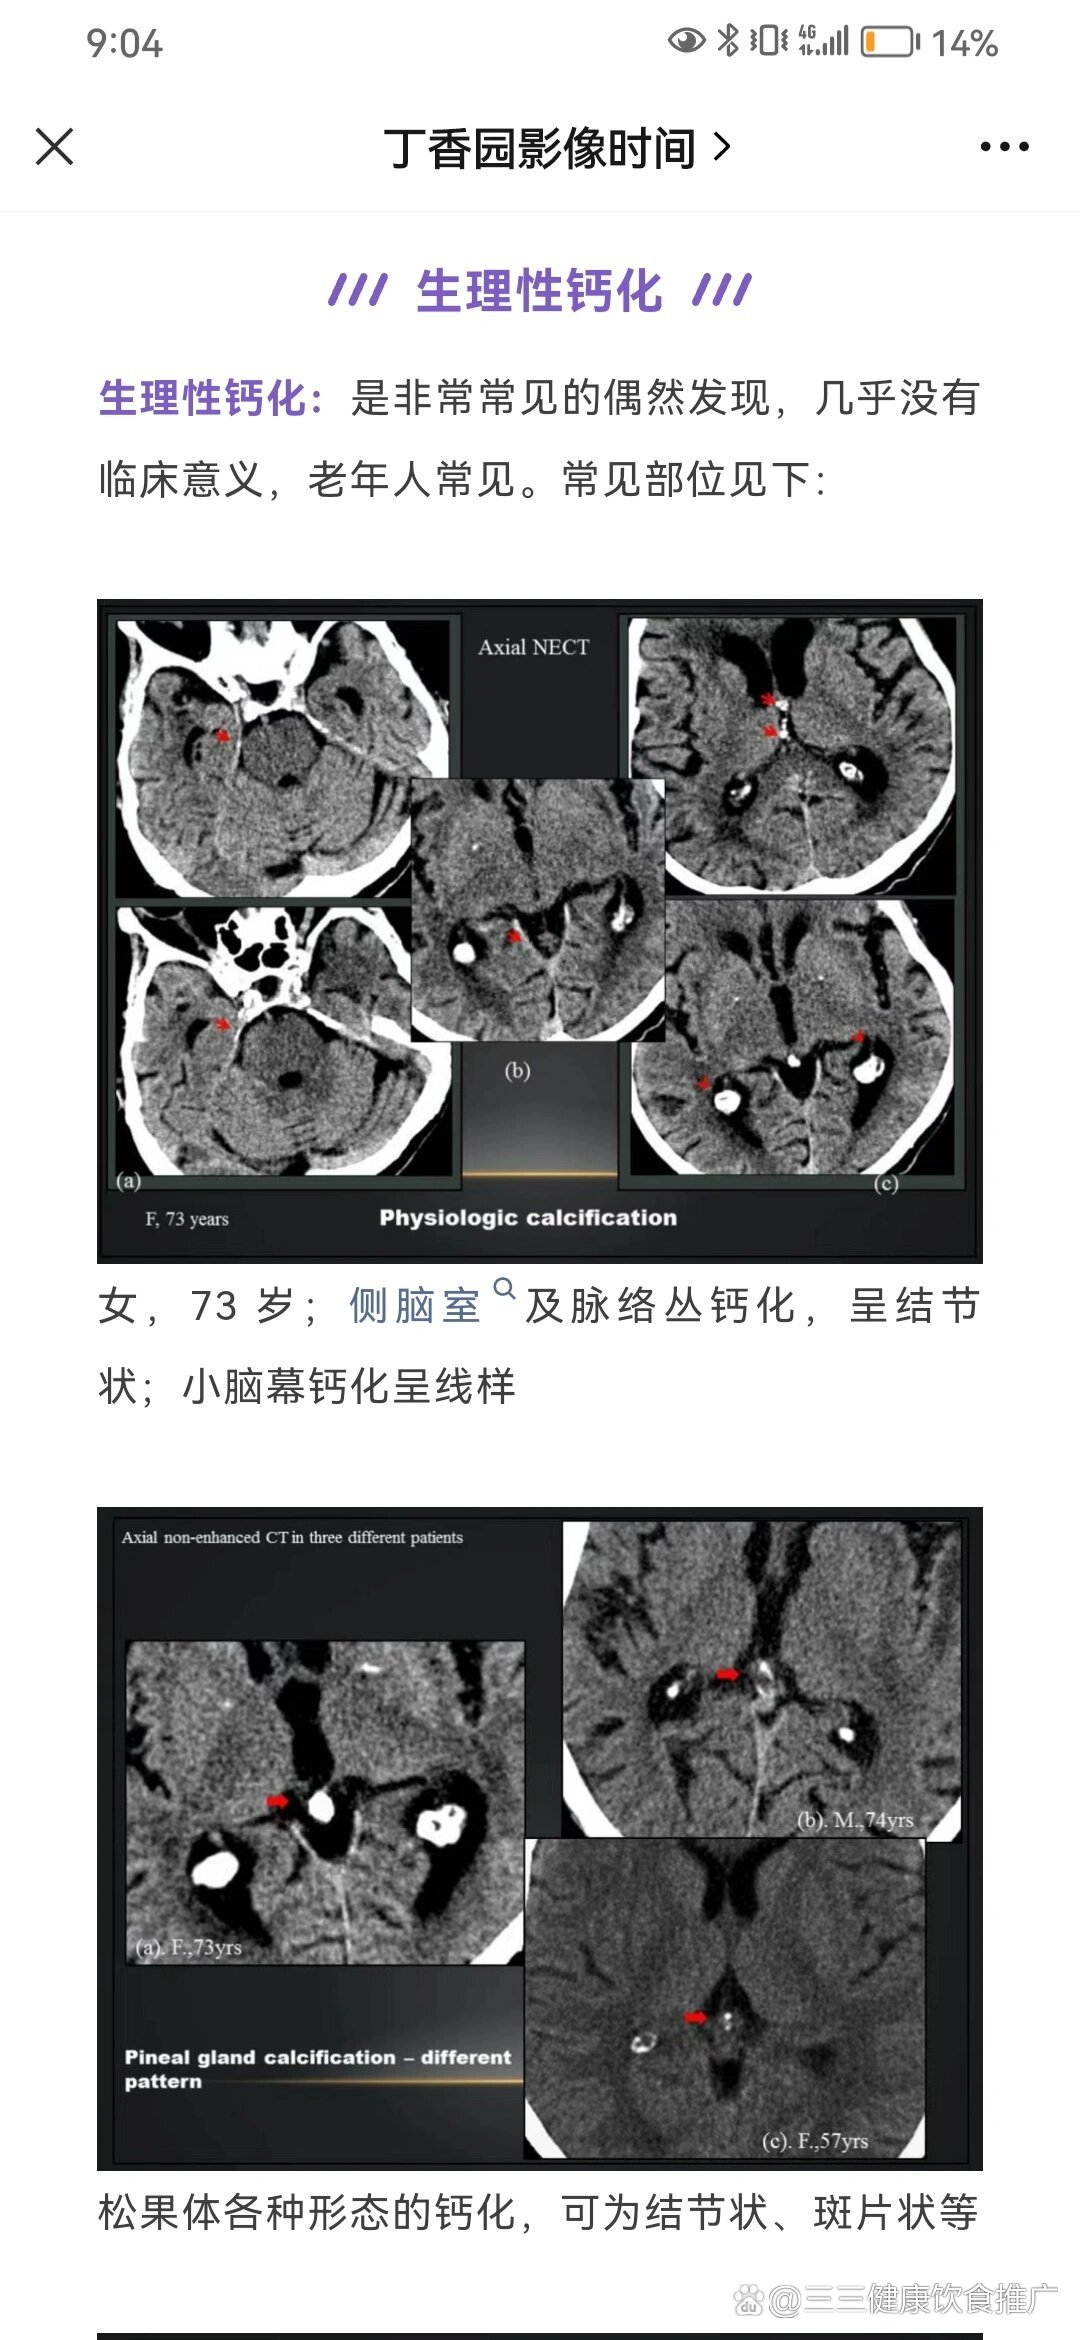

常见颅脑生理性钙化

主要见于侧脑室三角区,钙化呈圆形或不规则形,多数情况下脉络膜丛钙化